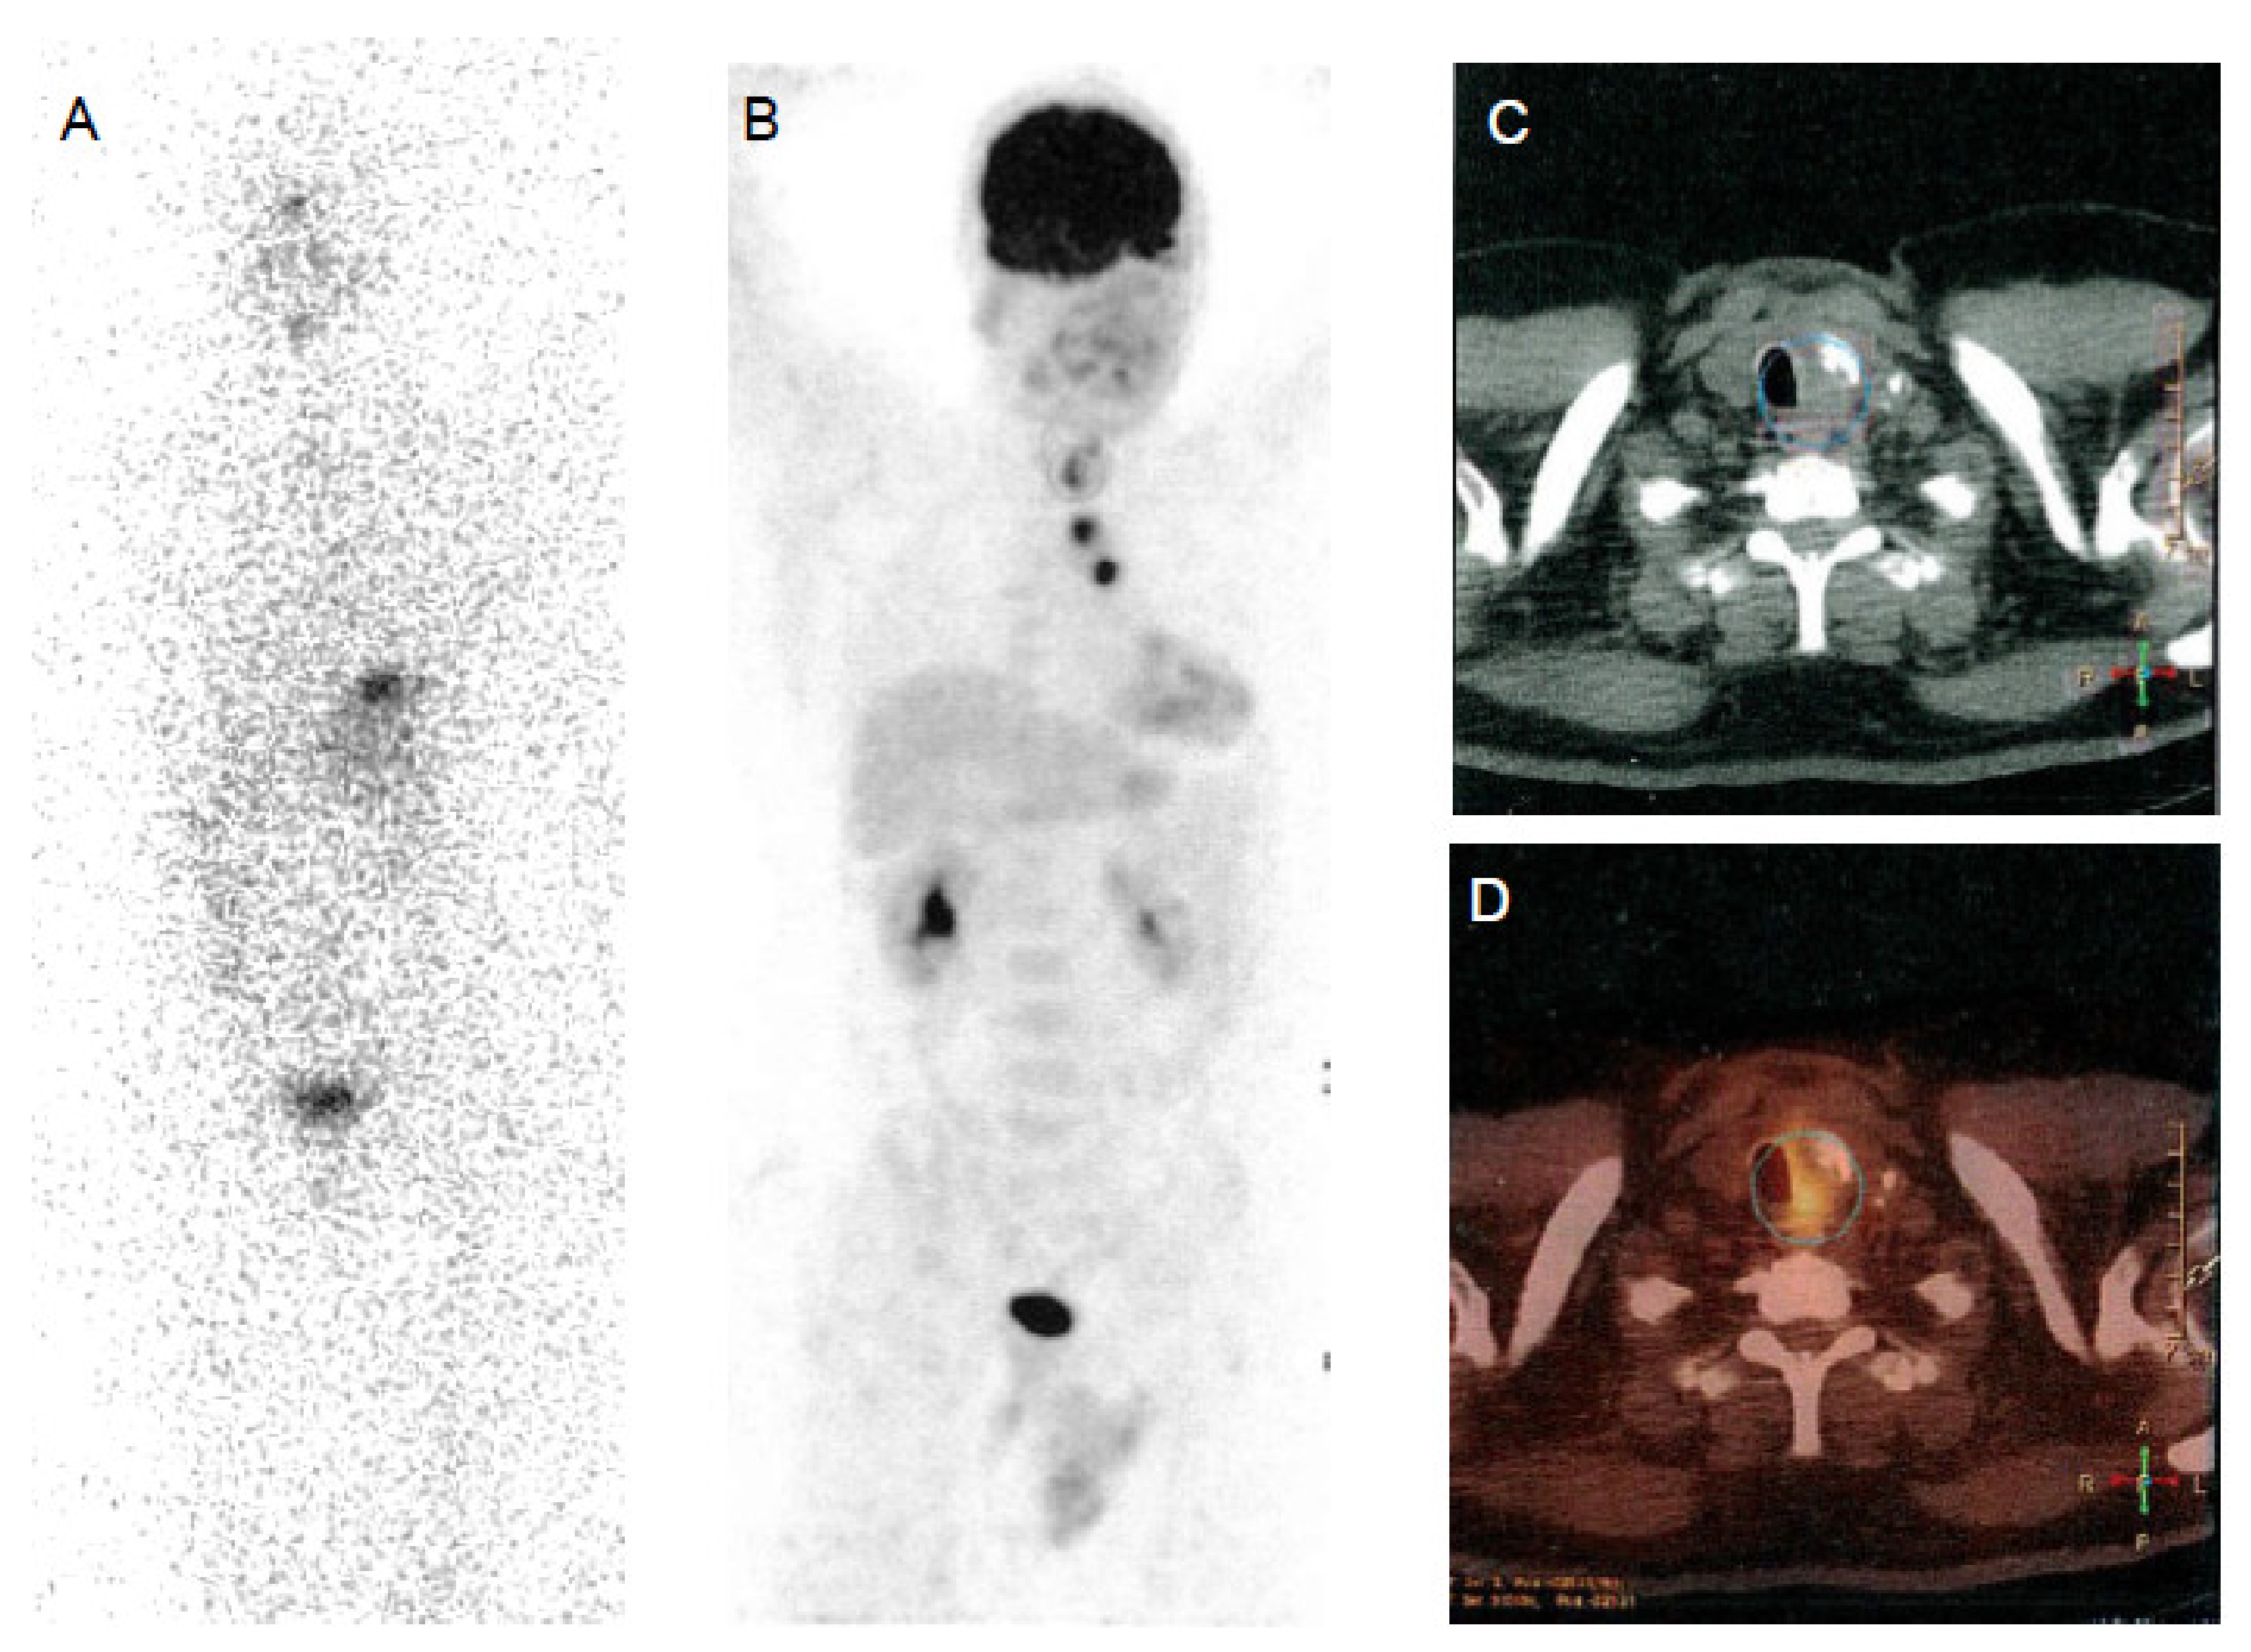

Figure 2.

Papillary thyroid cancer in a 30-year-old woman. Post-therapy (A) 131I whole-body scan and 18F-FDG PET-CT (B,C,D) images. Post-therapy 131I whole-body scan did not show areas of uptake (A). 18F-FDG PET-CT images evidenced multiple areas of increased uptake in the left retrosternal and latero-cervical region.

In DTC patients, the “flip-flop phenomenon” consists of a mismatch between high glucose and low iodine uptake, due to the elevated glucose metabolism coupled to the dedifferentiation process and has an important prognostic significance (Figure 2). This is observed in patients with iodine refractory thyroid cancer, with poorly differentiated, Hürthle cell cancer, PTC with aggressive features (tall cell variant) or with the BRAF V600E mutation and less frequently in patients with well differentiated papillary or follicular carcinoma. This indicates clinically more aggressive lesions [74,75,76] and the presence of 18F-FDG uptake in lesions with also radioiodine uptake indicates that these lesions are less likely to respond to radioiodine treatment [77].